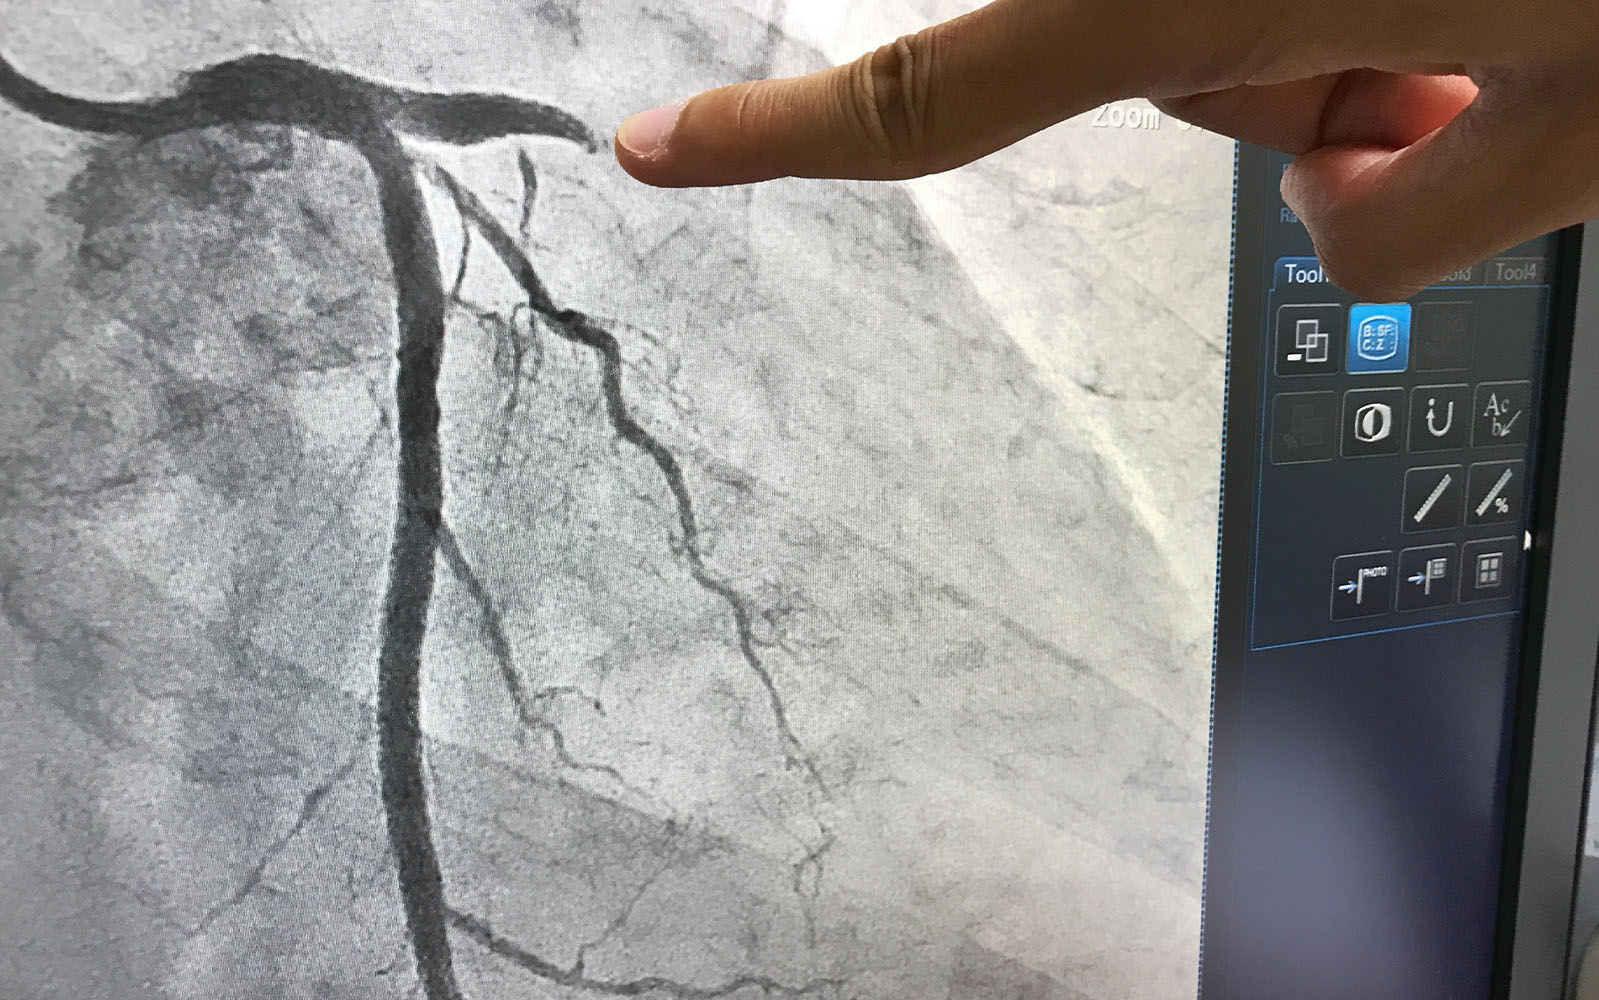

Prosedur kateterisasi jantung memiliki fungsi sebagai diagnostik maupun terapeutik. Yang dimaksud sebagai sarana diagnostik adalah pelaksanaan kateterisasi jantung untuk mengetahui kondisi maupun kelainan pada pembuluh darah dan jantung, juga tekanan serta kadar oksigen dalam jantung.

Kateterisasi jantung juga bisa membantu dokter menentukan rencana penanganan lebih lanjut bagi kondisi Anda. Selain itu, kateterisasi jantung sebagai proses terapeutik atau pengobatan juga bisa dilakukan untuk memasang ring jantung, ablasi, dan beberapa tindakan lain.

Dengan melakukan kateterisasi jantung, dokter spesialis jantung dan pembuluh darah bisa melihat kondisi maupun kerusakan jantung atau pembuluh darah dengan lebih akurat, terlebih jika dilengkapi dengan penggunaan Optical Coherence Tomography (OCT). Jika memang diperlukan pengambilan sampel jaringan, dokter bisa melakukannya dengan kateterisasi jantung.

Beberapa tindakan penanganan untuk mengatasi masalah pada jantung dan pembuluh darah pun bisa dilakukan dengan prosedur ini, termasuk dengan pemasangan ring jantung.